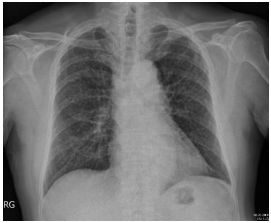

1. A 39-year-old man had this chest X-ray on his health exam. No any clinical symptoms.